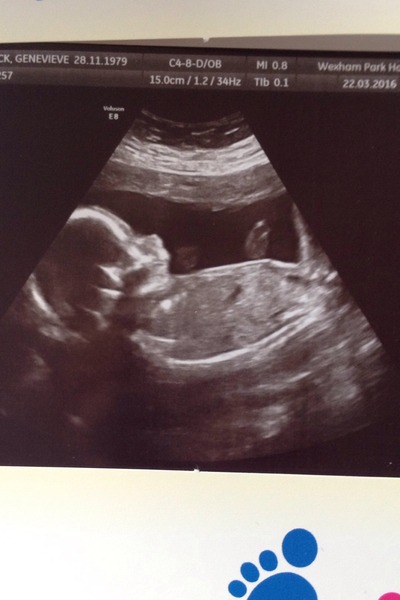

I had my scan today, it took about half an hour because the baby kept wiggling too much for the sonographer to get the measurements he needed. We also found out that it's a girl! I'm so excited, I was really hoping it would be. I celebrated with a little outfit from the M&S sale this afternoon.

I'm having a healthy little girl! Smile